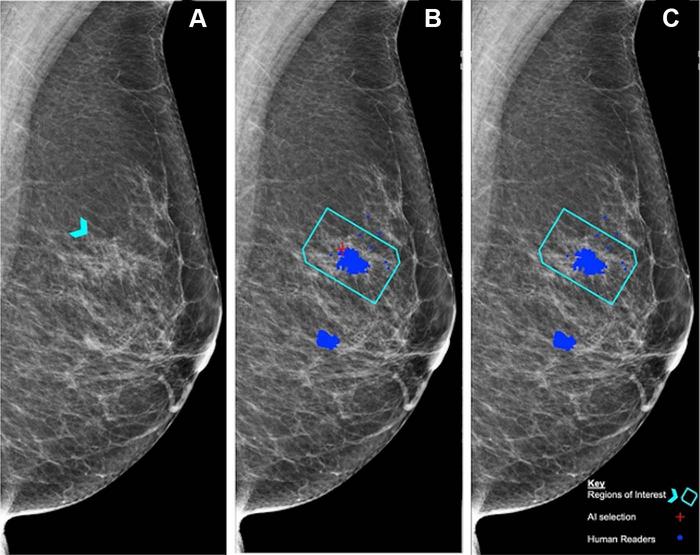

Left mediolateral oblique mammogram. Unadulterated mammogram shows an asymmetric density (arrowhead) which, after biopsy, was determined to be a histologic grade 2 ductal carcinoma. (B) Artificial intelligence (AI) has correctly marked the region of interest in the left breast for recall (red cross) when set at a recall threshold of 2.91 or higher to match average human specificity, demonstrating a true-positive case. (C) AI has not marked the region of interest in the same breast when set at a recall threshold of 3.06 or higher, indicating a false-negative case. Blue dots indicate findings identified by the human readers. This shows how modifying the threshold for recall can impact the sensitivity of the AI model. Source: Personal Performance in Mammographic Screening via Yan Chen.